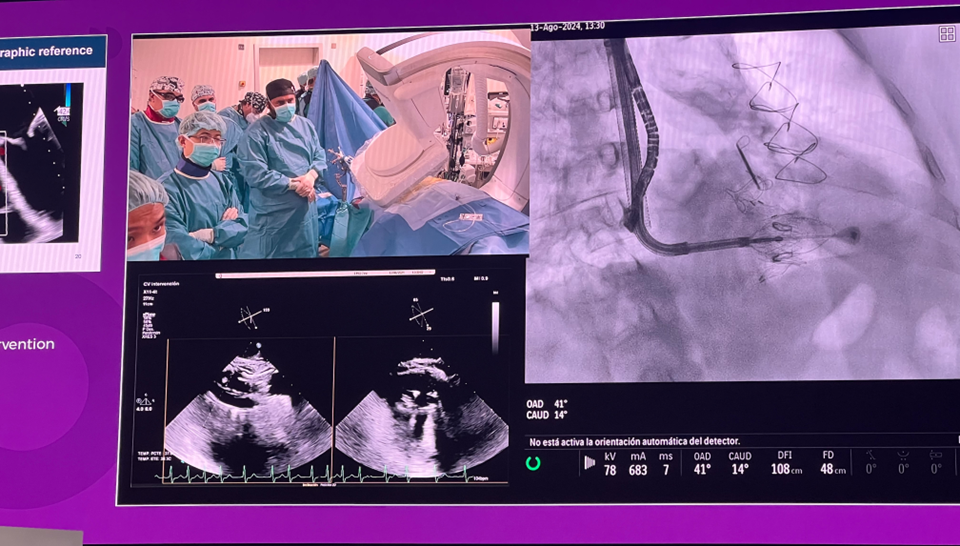

隨后由來自西班牙維哥-阿爾瓦羅昆奎羅醫(yī)院(Hospital Álvaro Cunqueiro, Vigo, Spain)的 Rodrigo Estevez-Loureiro 教授在大會主會場的經(jīng)導(dǎo)管介入瓣膜新技術(shù)環(huán)節(jié),帶來了一例 LuX-Valve Plus 手術(shù)錄播,對手術(shù)植入的步驟和關(guān)鍵要點進(jìn)行了詳細(xì)深入的介紹。同時,臺上的多位討論嘉賓也結(jié)合他們的 LuX-Valve Plus 手術(shù)經(jīng)驗進(jìn)行了深入的探討。來自香港瑪麗皇后醫(yī)院(Queen Mary Hospital, Hong Kong, China)的 Simon Lam 教授分享了 LuX-Valve Plus 在術(shù)前有起搏導(dǎo)線病人中的植入經(jīng)驗,來自巴西圣保羅(Rede D'Or São Luiz, São Paulo, Brazil)的 Vinicius Esteves 教授補(bǔ)充了 LuX-Valve Plus 獨特的非徑向支撐力設(shè)計,能夠?qū)崿F(xiàn)非常低的術(shù)后起搏器植入率,來自法國波爾多大學(xué)醫(yī)院(CHU de Bordeaux, Bordeaux, France)的 Lionel Leroux 教授則分享了其在LuX-Valve Plus歐洲臨床試驗過程中,對于大尺寸瓣環(huán)植入的優(yōu)異結(jié)果。